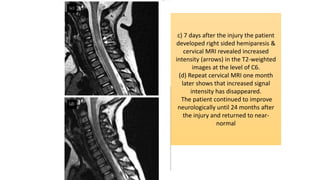

c) 7 days after the injury the patient

developed right sided hemiparesis &

cervical MRI revealed increased

intensity (arrows) in the T2-weighted

images at the level of C6.

(d) Repeat cervical MRI one month

later shows that increased signal

intensity has disappeared.

The patient continued to improve

neurologically until 24 months after

the injury and returned to near-

normal